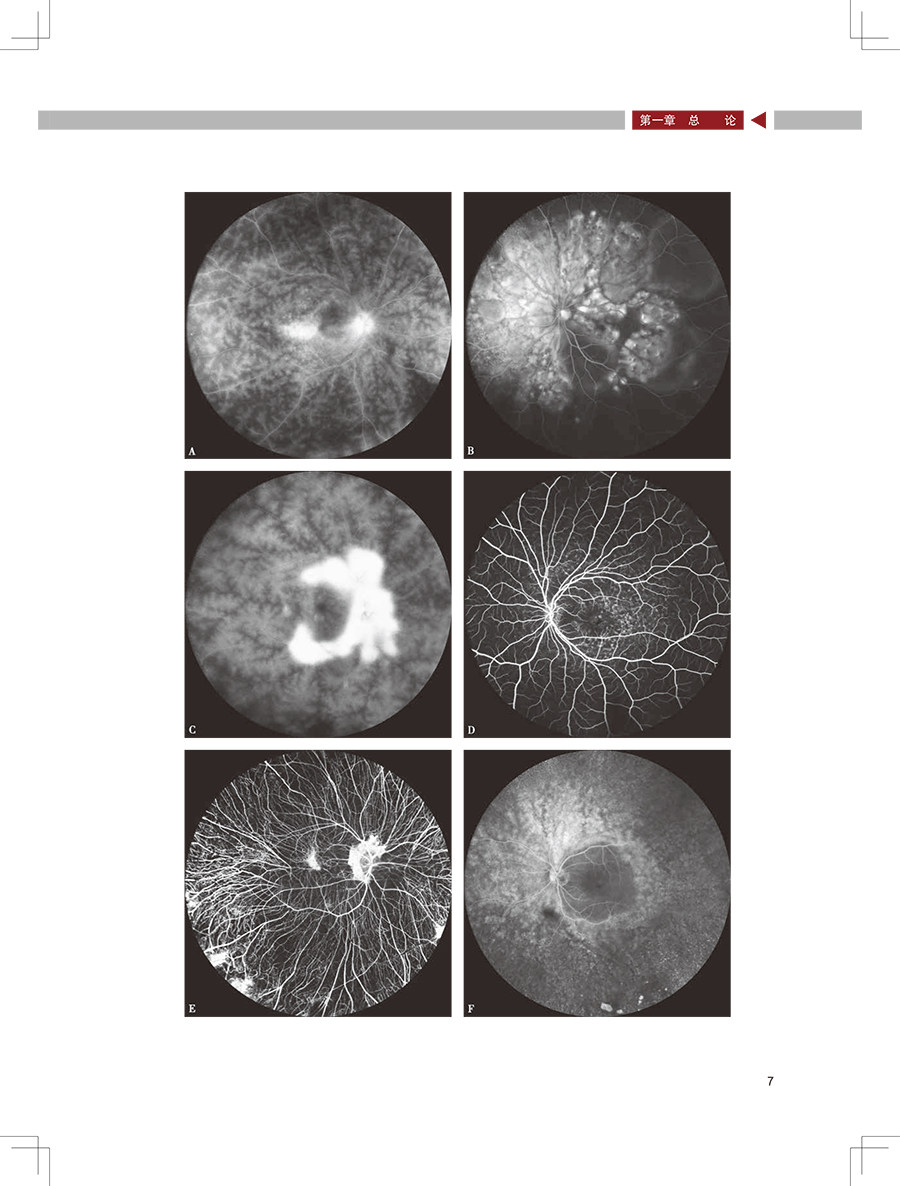

本书延续“图说眼科系列”的风格,以各类眼底病为线,向读者展示广角眼底影像在眼底病诊疗中的应用,辅以图片注释,以及特色的图片点评,突出广角影像技术在各类眼底病中的优势,将为广大眼科医生及眼底病专科医生更好地掌握广角眼底影像技术提供帮助,尤其是疑难眼底病的诊治提供指导。 本书延续“图说眼科系列”的风格,以各类眼底病为线,向读者展示广角眼底影像在眼底病诊疗中的应用,辅以图片注释,以及特色的图片点评,突出广角影像技术在各类眼底病中的优势,将为广大眼科医生及眼底病专科医生更好地掌握广角眼底影像技术提供帮助,尤其是疑难眼底病的诊治提供指导。